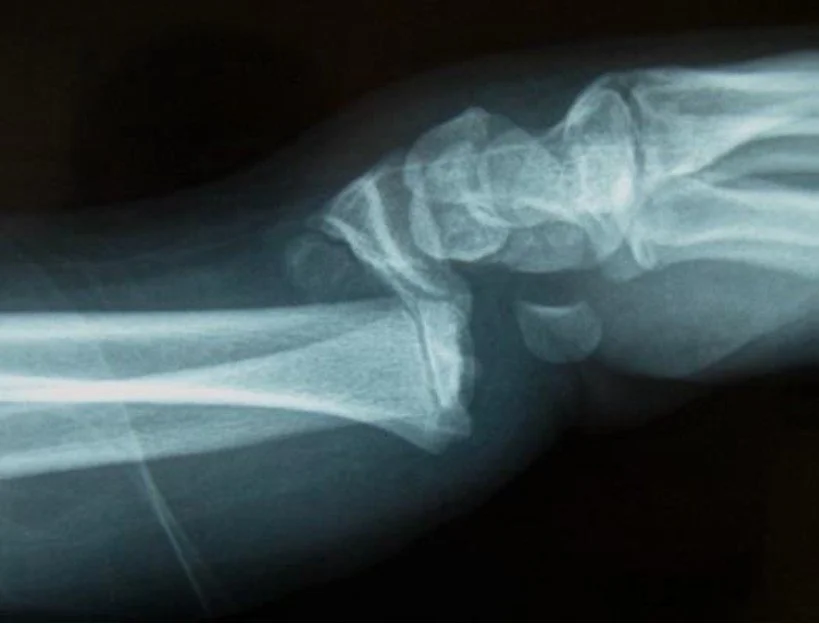

Arthritis Wrist and Forearm Childrens Wrist Fractures Colles Fractures Colles Surgery Chronic Forearm Compartment Syndrome De Quervains Syndrome Kienbocks Disease Scaphoid Fractures Scpholunate Ligament Tears TFC Tears Wrist Arthritis - Salvage Procedures Wrist Arthroscopy Wrist Exercises Wrist Xrays - Radiographers